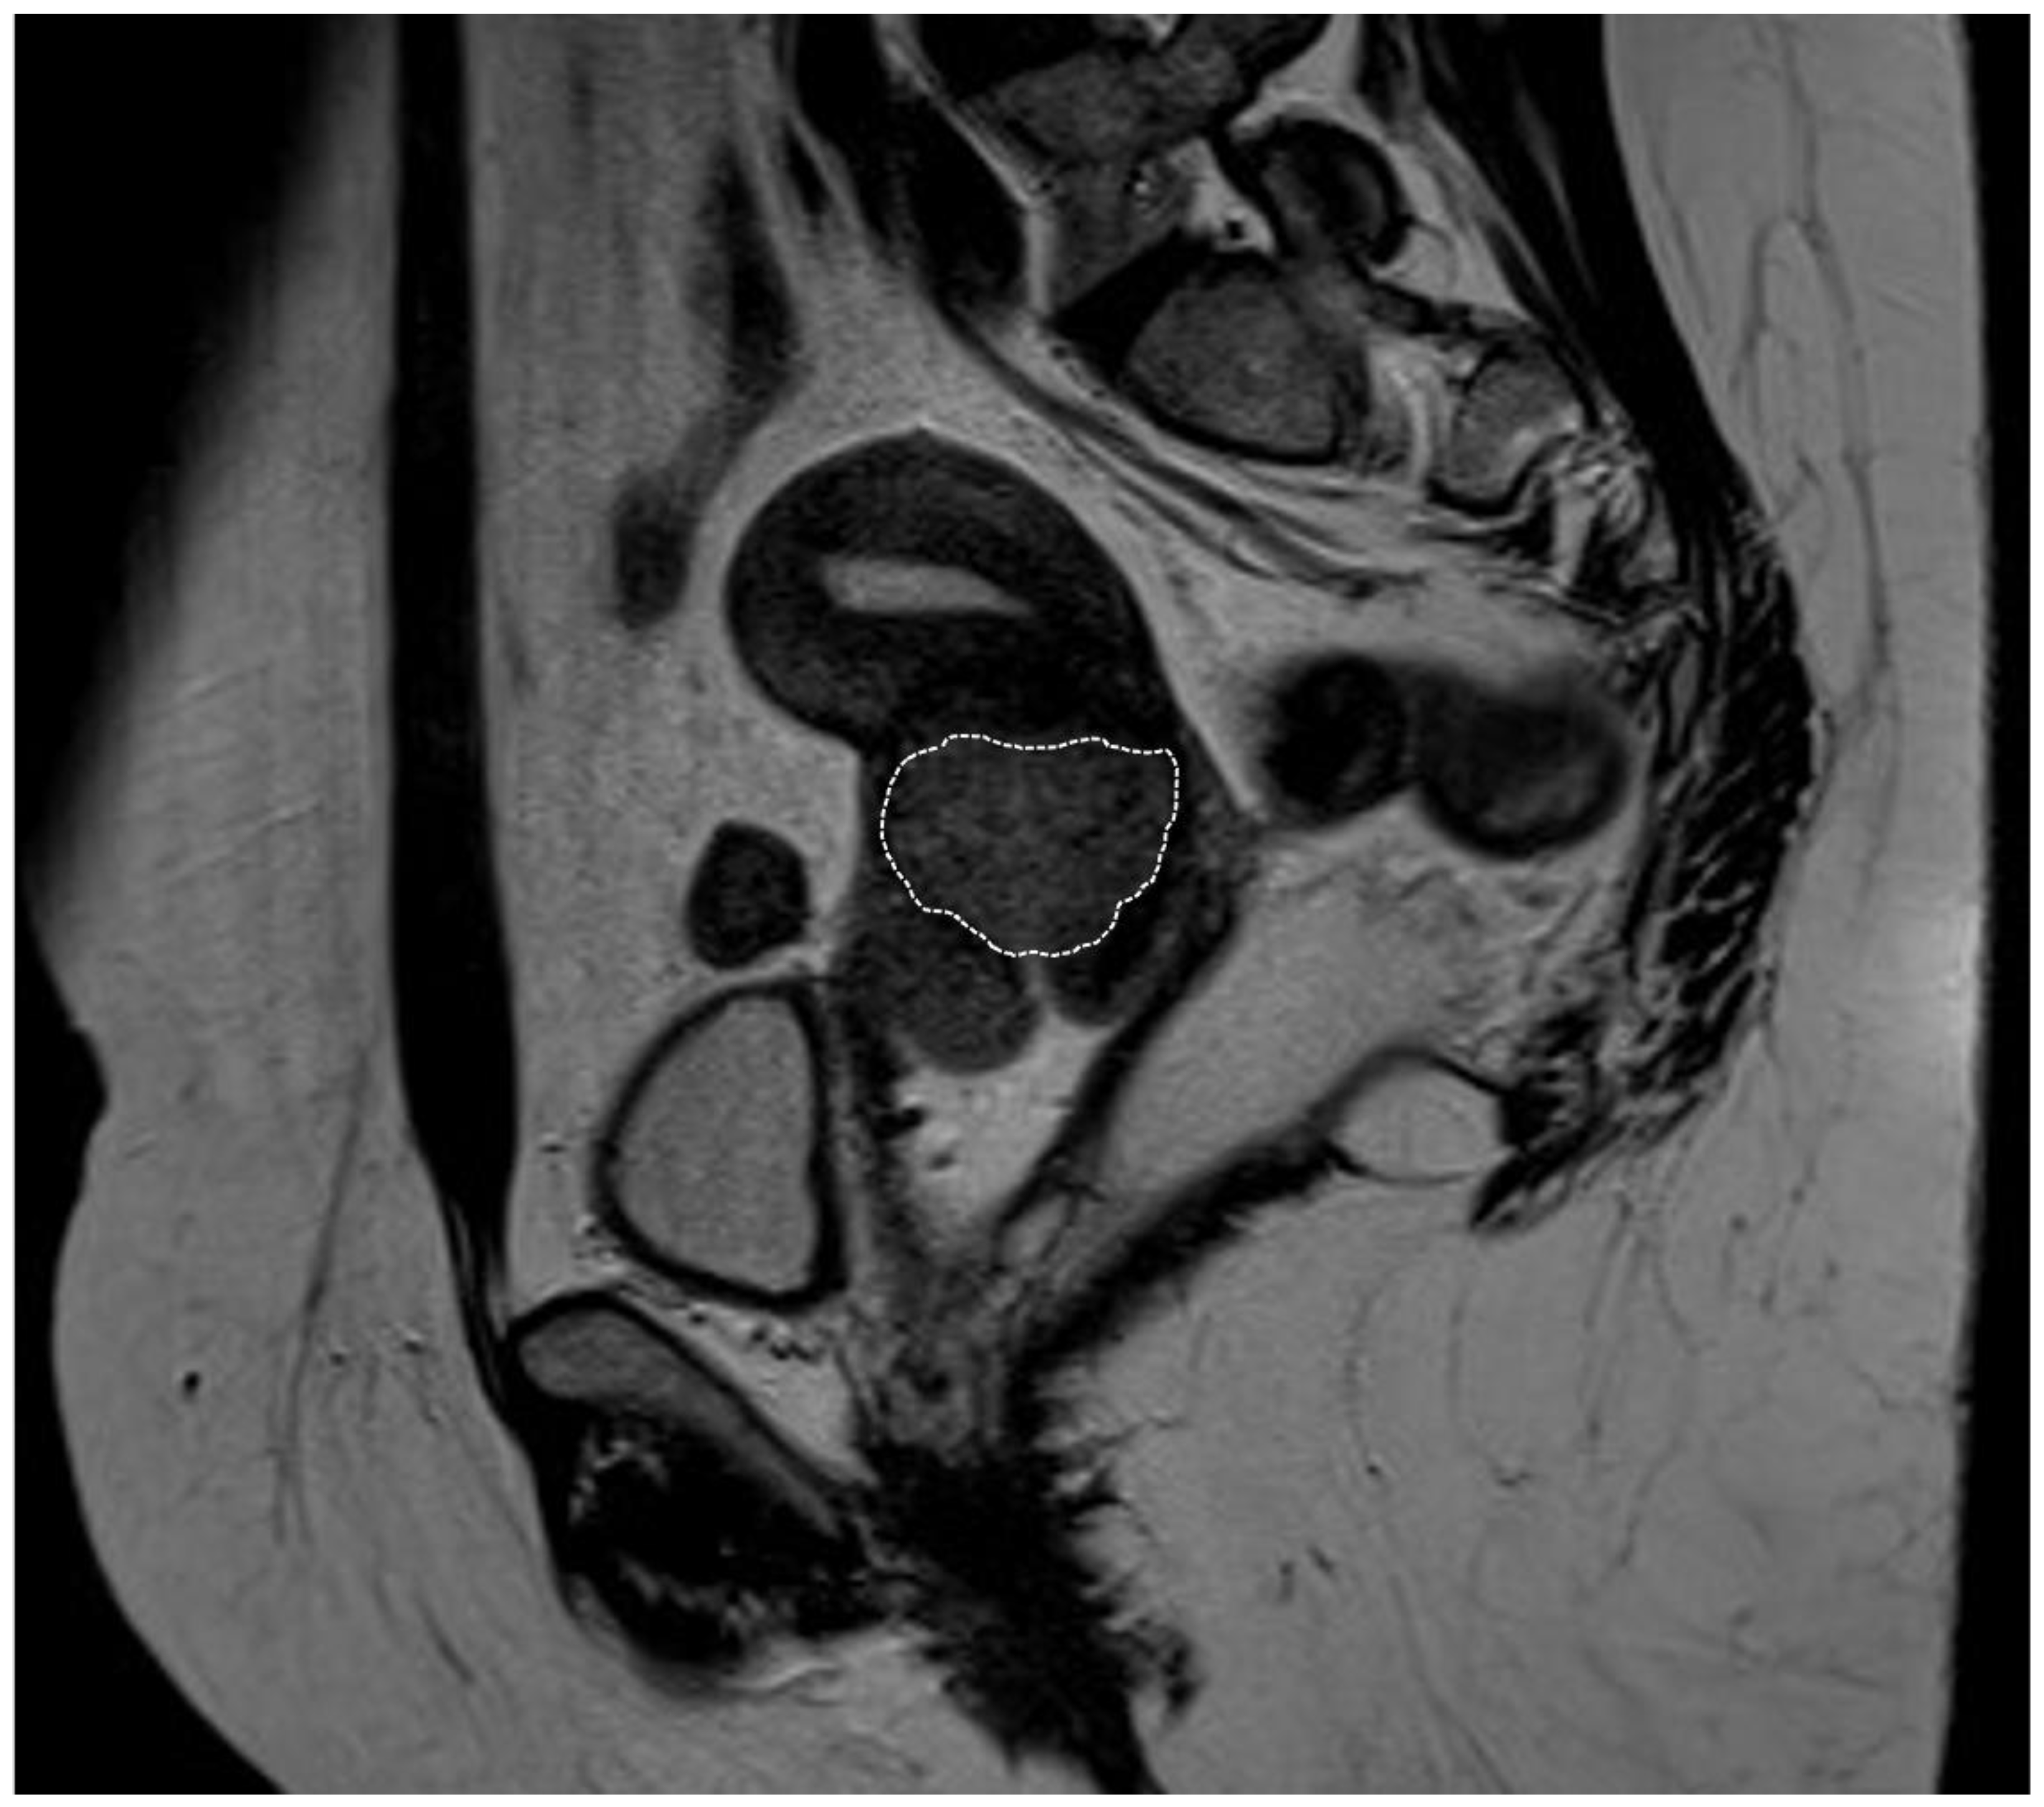

Figure 1.

Pelvic magnetic resonance imaging of a bulky cervical tumor (marked with the dotted circle). The image corresponds to a 43-year-old patient diagnosed with cervical squamous cell carcinoma, with tumor dimensions of 43 × 41 × 39 mm on imaging and no parametrial involvement. She underwent primary surgical treatment with bilateral pelvic lymphadenectomy and radical hysterectomy (in 2015), with a postoperative stage of IIA2 (FIGO 2018). Adjuvant treatment with external beam radiotherapy (EBRT), chemotherapy (CT), and brachytherapy (BT) was administered. She was disease-free at the time of writing this article.